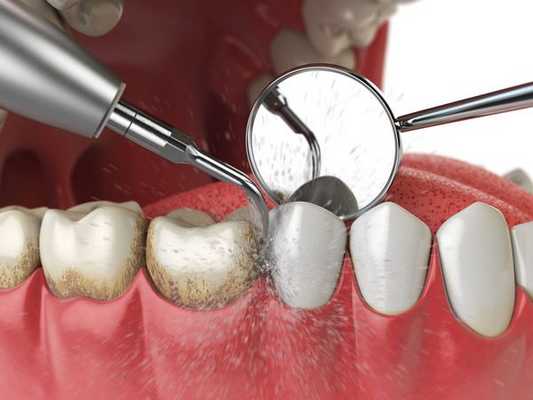

Для успешного лечения нужно в первую очередь устранить причину воспаления. С этой целью обязательно проводится удаление налёта и зубного камня.

При начальных стадиях заболевания этой процедуры и использования местных антисептиков достаточно. Для снятия воспаления используется метронидазол, хлоргексидин, настои шалфея и ромашки. Для улучшения регенерации показано местное применение "Солкосерила", облепихового масла.

Выбор индивидуальной схемы лечения заболеваний пародонта зависит от этиологии и степени тяжести поражения. При пародонтите назначают профессиональную чистку, ревизию пародонтальных карманов, противовоспалительную и антибиотикотерапию. Из хирургических вмешательств в стоматологии проводят кюретаж, гингивотомию. Зубы 3-4 степени подвижности подлежат удалению. Действенными ортопедическими мероприятиями при заболеваниях пародонта являются шинирование и избирательное пришлифовывание.